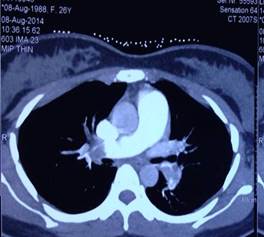

Tắc động mạch phổi cấp được nghi ngờ là nguyên nhân gây sốc, vì bệnh nhân có đau ngực, khó thở, nhịp tim nhanh, có thai 12 tuần và lâm sàng, điện tim có biểu hiện suy tim phải cấp. Chỉ định chụp cắt lớp vi tính (CLVT) động mạch phổi cấp cứu được xem xét. Theo Uỷ ban quốc tế về an toàn phóng xạ (The International Commission of Radiologic Protection), liều tia xạ khi chụp CLVT động mạch phổi phóng qua tử cung người mẹ không làm tăng nguy cơ tử vong hoặc dị tật thai nhi [1]. Bệnh nhân được chụp CLVT 64 dãy động mạch phổi, kết quả cho thấy huyết khối ở cả 2 động mạch phổi phải và trái với mức độ nặng (SI) CLVT là 50%.

Hình 3: Huyết khối ở động mạch phổi phải và trái (SI : 50%)